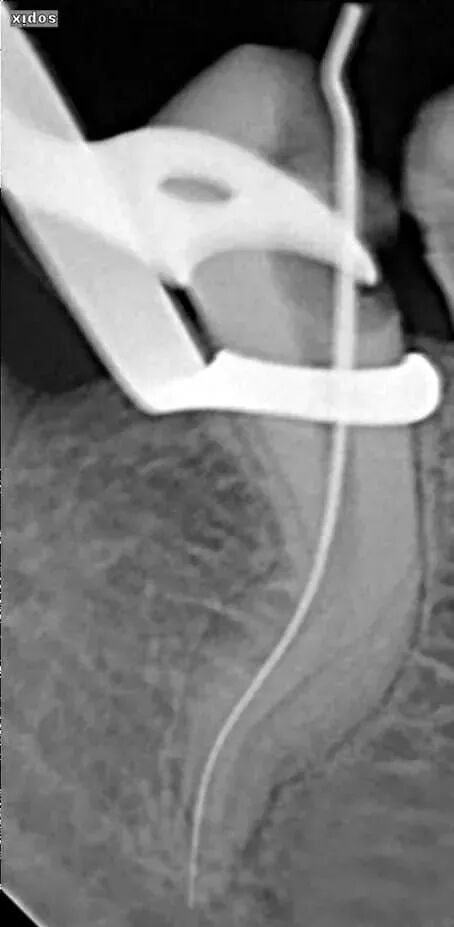

测定根管长度用以下三种方法结合:x片法、根测仪测量、手感法。建议首要以根测仪(COXO宇森医疗根测仪个人体验和进口的没什么区别,测量数据很准确,稳定性不错,支持国货)为准。

但是对于以下三种情况根测仪可能出现不准确,所以建议拍初挫片:

a、根尖孔破坏或根尖孔较大的患牙。

b、根尖暗影较大的患牙。

c、经过一次不彻底拔髓后有残髓的患牙。